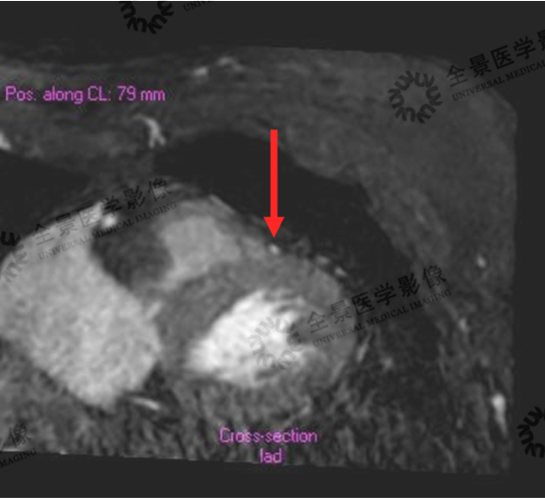

一位中年女性,前胸、后背疼数月,心脏彩超显示无异常,心电图平板运动实验显示为阳性,因自身过敏体质无法做心脏冠脉CTA明确病症,而无创心脏冠状动脉磁共振检查解决了这一问题。

心脏冠状动脉VR

局限性浅肌桥